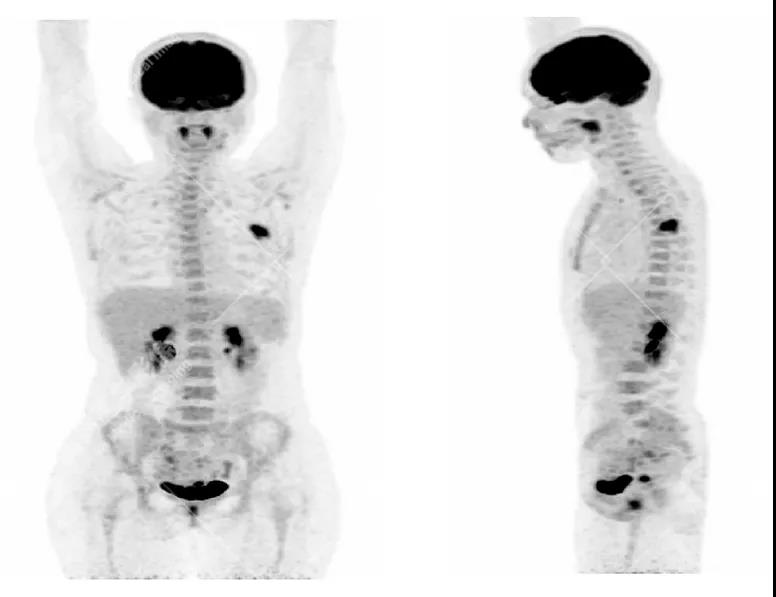

女性 67歲 因背痛查體,糖尿病11年。腫瘤標(biāo)記物:CEA 6.4↑,AFP、CA125、CA199正常。外院MR檢查:胸11椎體-附件左份異常信號,增強環(huán)狀強化,骨原發(fā)?轉(zhuǎn)移?感染?PET/CT影像圖

胸椎溶骨性骨質(zhì)破壞,F(xiàn)DG環(huán)狀代謝增高,SUVmax為4.0。

左側(cè)乳腺一軟組織結(jié)節(jié),F(xiàn)DG代謝增高,SUVmax為2.6。

最終診斷:左側(cè)乳腺癌伴胸椎單發(fā)骨轉(zhuǎn)移。